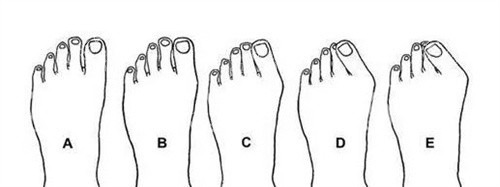

目前拇外翻的手术方法有上百种,每种手术都有其适用范围和局限性。如果医生在术前没有对患者的拇外翻程度、足部骨骼结构、关节稳定性等因素进行齐全、较准的评估,选择了不适合患者的手术方案,就可能导致矫正不干净,为复发埋下隐患。

比如,对于轻度拇外翻患者,如果采用了过于激进的手术方式,可能会破坏足部的正常结构和稳定性;而对于重度拇外翻患者,如果选择的手术方式矫正力度不够,就无法有效纠正畸形,术后复发的概率自然会增加。所以,在选择手术时,一定要找可靠的足踝外科医生,进行详细的检查和评估,制定个性化的手术方案。